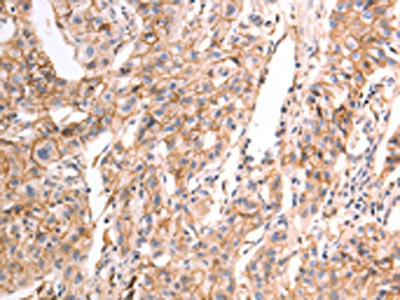

The image on the left is immunohistochemistry of paraffin-embedded Human breast cancer tissue using CSB-PA908796(pan CDH Antibody) at dilution 1/20, on the right is treated with synthetic peptide. (Original magnification: ×200)

The image on the left is immunohistochemistry of paraffin-embedded Human lung cancer tissue using CSB-PA908796(pan CDH Antibody) at dilution 1/20, on the right is treated with synthetic peptide. (Original magnification: ×200)